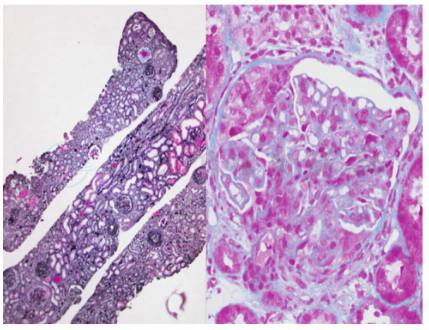

入院后行肾活检,肾活检病理学检查:荧光:IgG(++),IgM(++),IgA(++),C3(++),C1q(++),FRA(++),在系膜区及毛细血管壁颗粒状沉积(图 1);光镜:肾穿刺可见 15个肾小球。肾小球系膜细胞及内皮细胞弥漫增生,内皮下及系膜区可见嗜复红蛋白沉积。可见7个细胞性新月体,2个细胞纤维性新月体形成。肾小管多灶状萎缩,肾间质多灶状淋巴及单核细胞浸润伴灶状纤维化。小动脉管壁轻度增厚。符合Ⅳ型狼疮性肾炎(Ⅳ-G(A/C)及Ⅱ型新月体性肾炎的诊断(图2);电镜:内皮下及系膜区可见电子致密物沉积,上皮细胞足突大部分融合(图3)。

图2 狼疮性肾炎:A:肾小球多数新月体形成(PASM×100),B:光肾小球系膜细胞及内皮细胞增生,内皮下及系膜区可见嗜复红蛋白沉积,伴细胞性新月体形成(PASM+Masson×400)